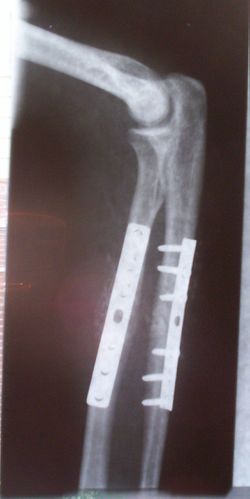

غرسات العظام لإصلاح الكسور في الكعبرة والزند. لاحظ الكسر المرئي في عظم الزند. (الساعد الأيمن)

تقويم العظام

تساعد زراعة العظام في التخفيف من مشاكل عظام ومفاصل الجسم. يتم استخدامها لعلاج كسور العظام ، والتهاب المفاصل ، والجنف ، وتضيق العمود الفقري ، والألم المزمن . تشمل الأمثلة مجموعة متنوعة من المسامير والقضبان والبراغي والألواح المستخدمة لتثبيت العظام المكسورة أثناء الشفاء..[1][2][3]